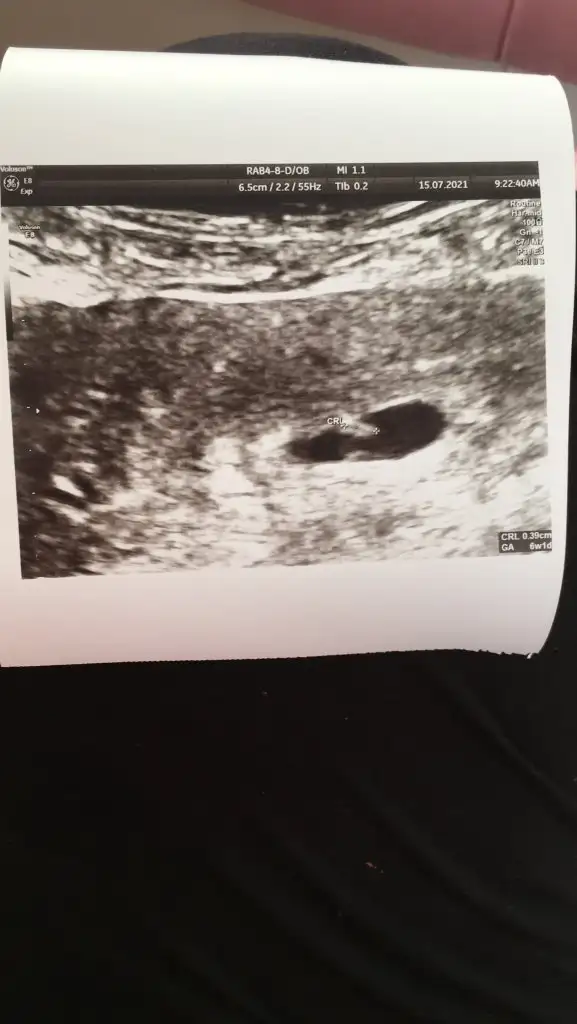

Banada ramzi tahmini yaparmisiniz karindan ultrasyon

Merhaba 👋 karından ultrason 6hafta1 günlük görüntü bu şekilde 🎈bu teoriye göre ne oluyor acaba bilgisi olan yazabilir mi 🙏